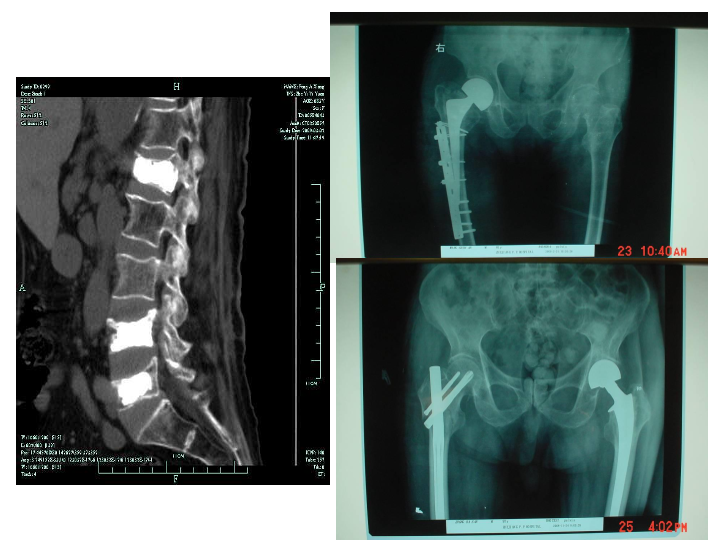

骨质疏松症的诊断和治疗